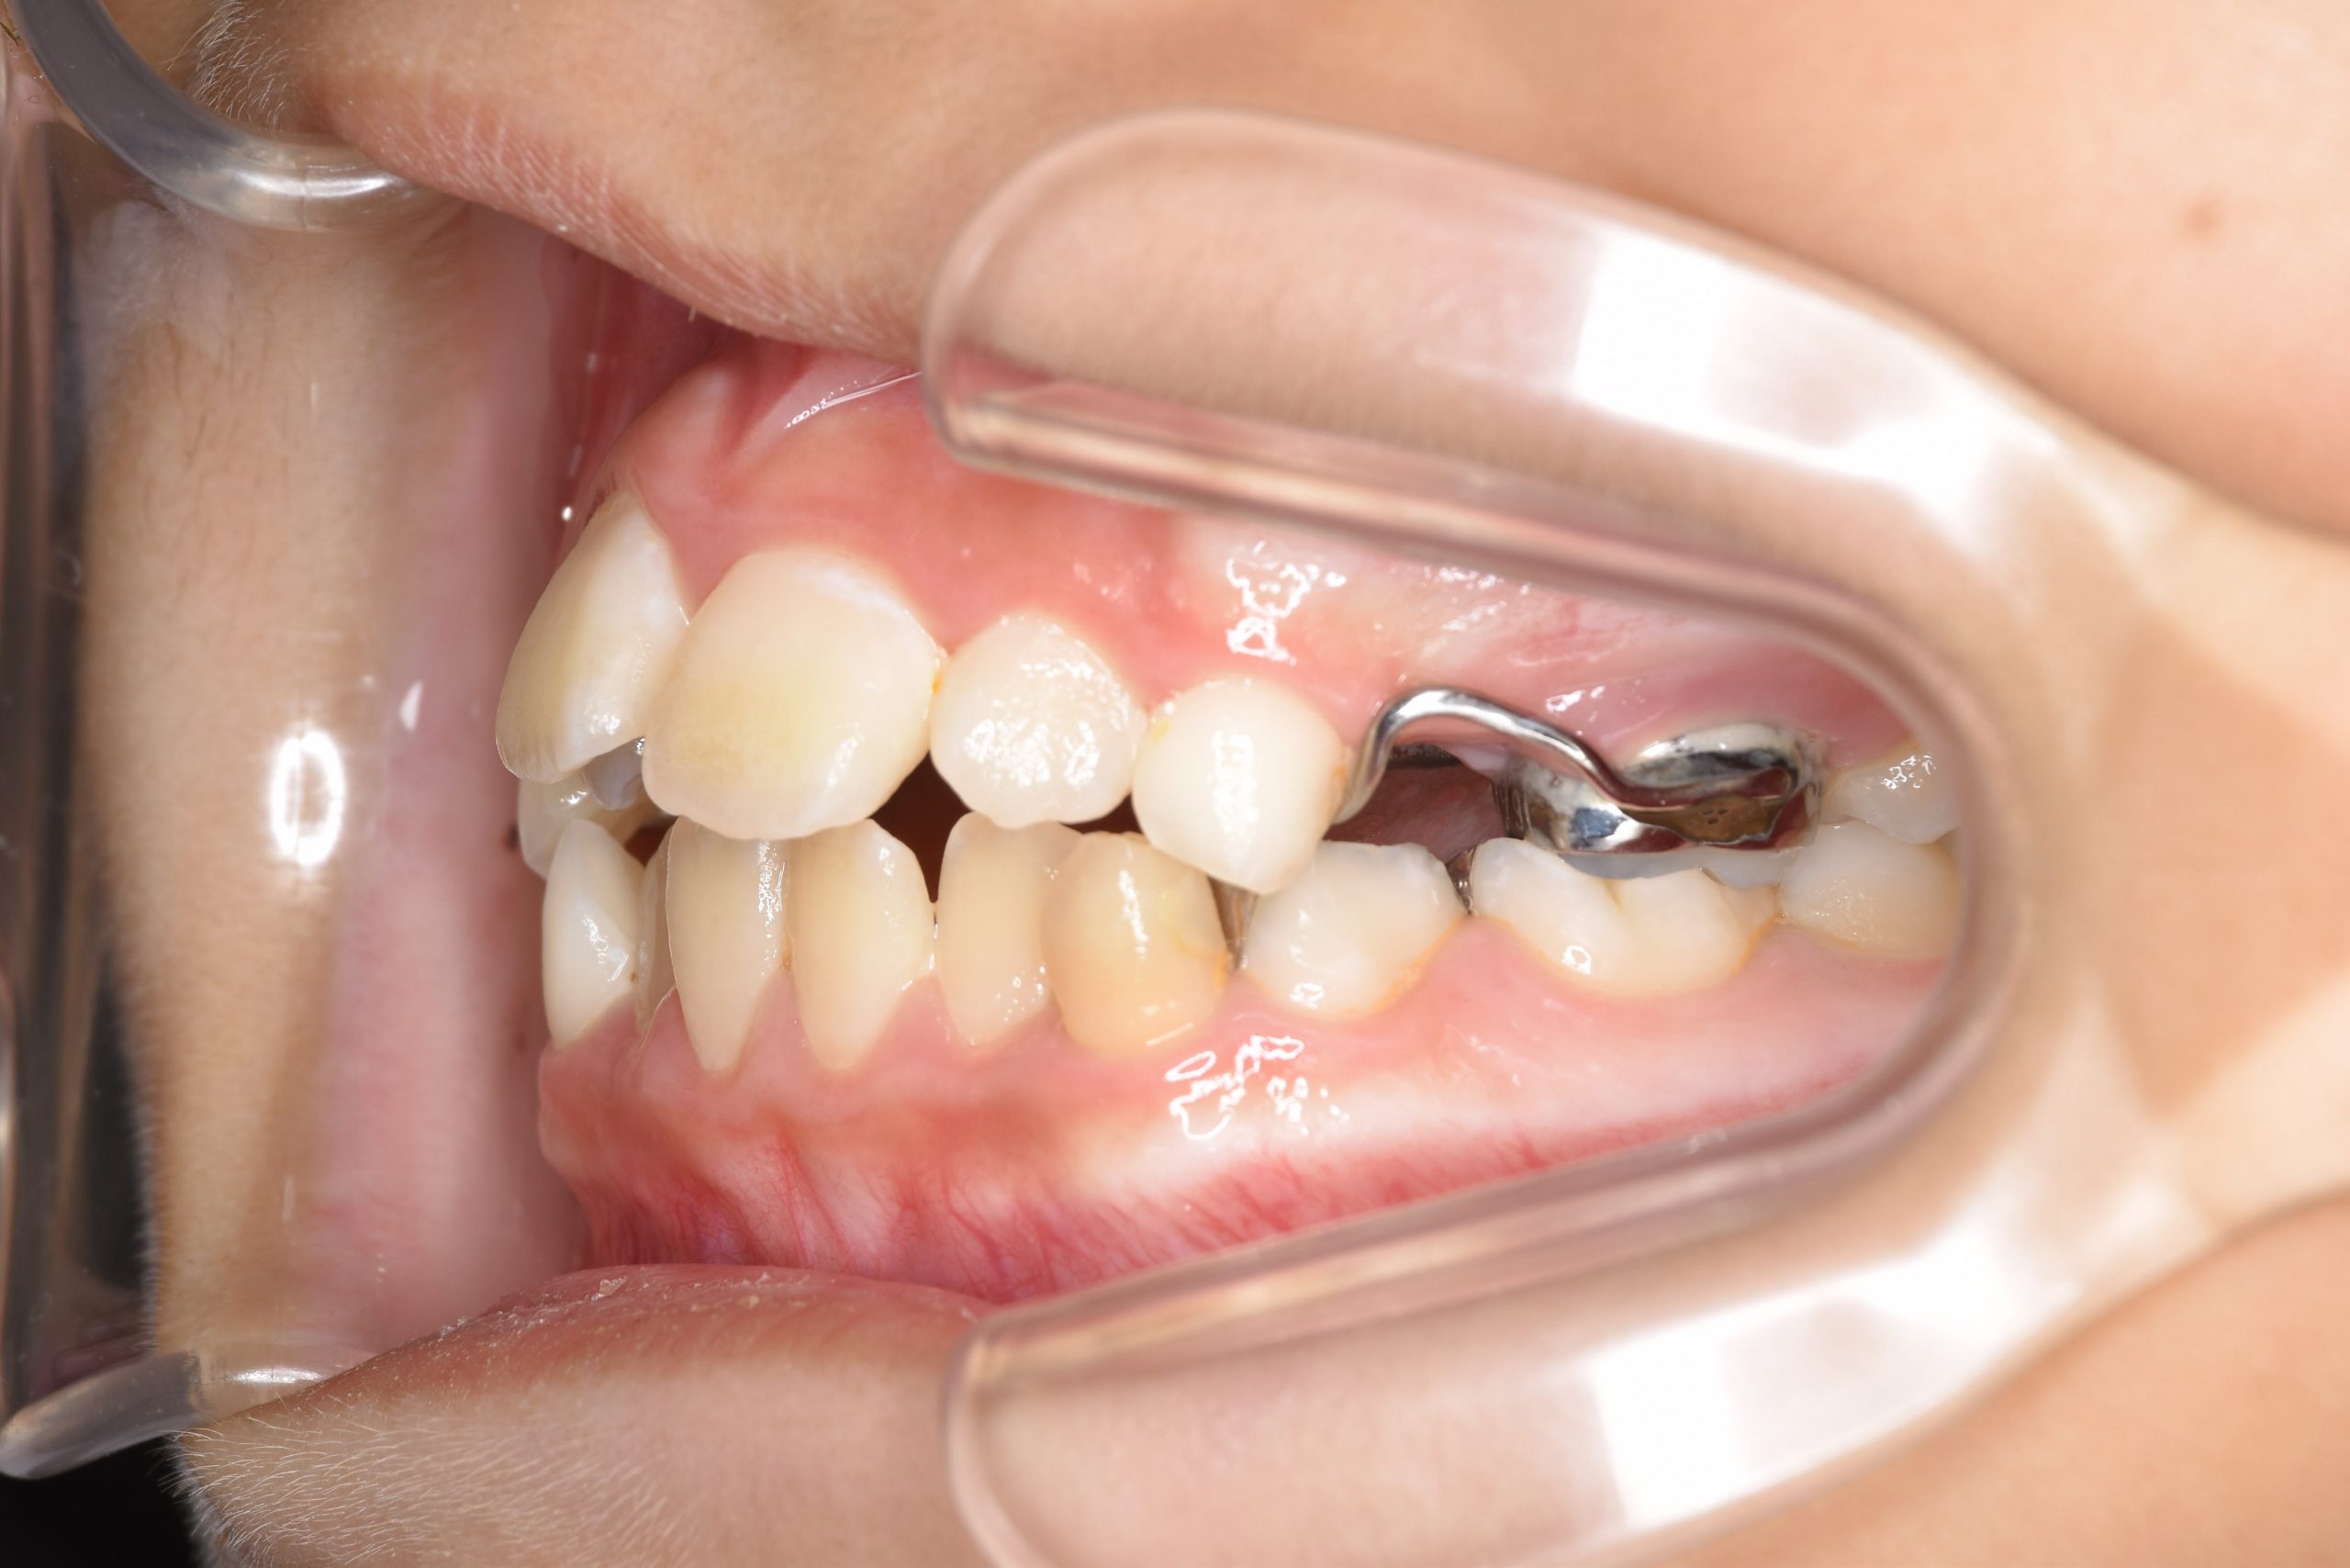

ビフォー

子どもの矯正治療|症例_169

主訴 歯並び|嚙み合わせ|口呼吸

施術内容 上顎急速拡大装置と下顎リンガルアーチを用いて上下顎骨を拡大した。

その後マウスピース型矯正装置で歯牙を配列し良好な咬合を獲得した。